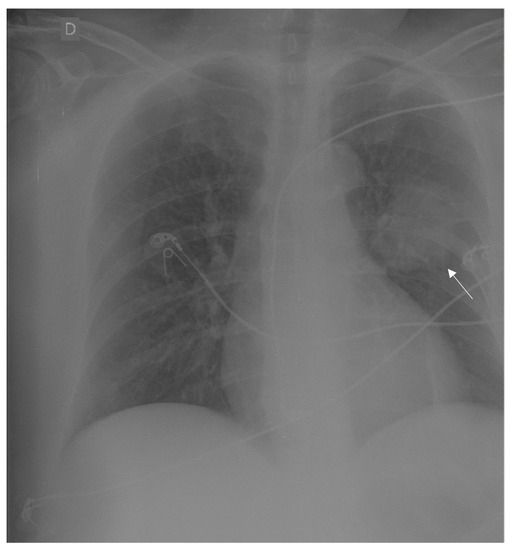

2. Case Report